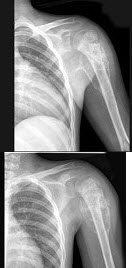

77、单项选择题

男,28岁,右肱骨上段肿痛1个月,疼痛以夜间明显,摄片如图所示,提示骨肉瘤最为主要的征象是()

A.溶骨性破坏

B.骨膜增生

C.肿瘤骨形成

D.软组织肿块影

E.Codman三角

78、单项选择题 肘关节侧位摄影,叙述错误的是()